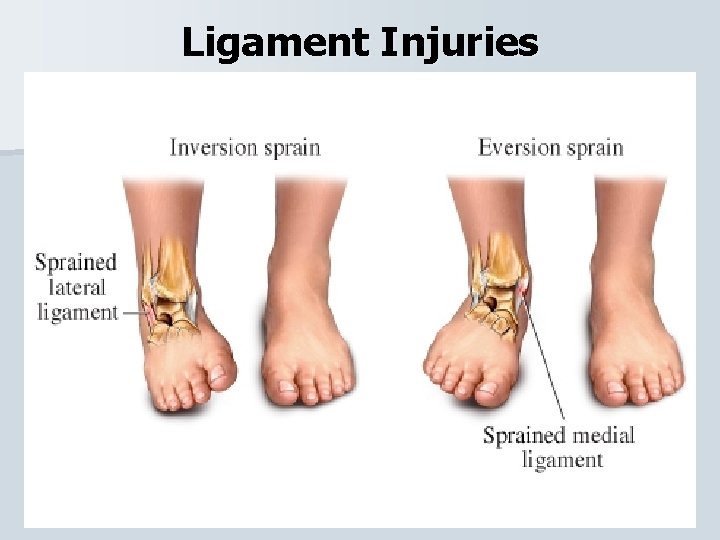

Ligament Injuries Lateral and Medial Ankle Sprain Majority of ankle sprains occur Inversion (85%) where Eversion (15%). • When the ankle inverts the lateral ligament are injured (ATF and calcaneofibular) and when it everts the medial ligamant (deltoid) is injured. •